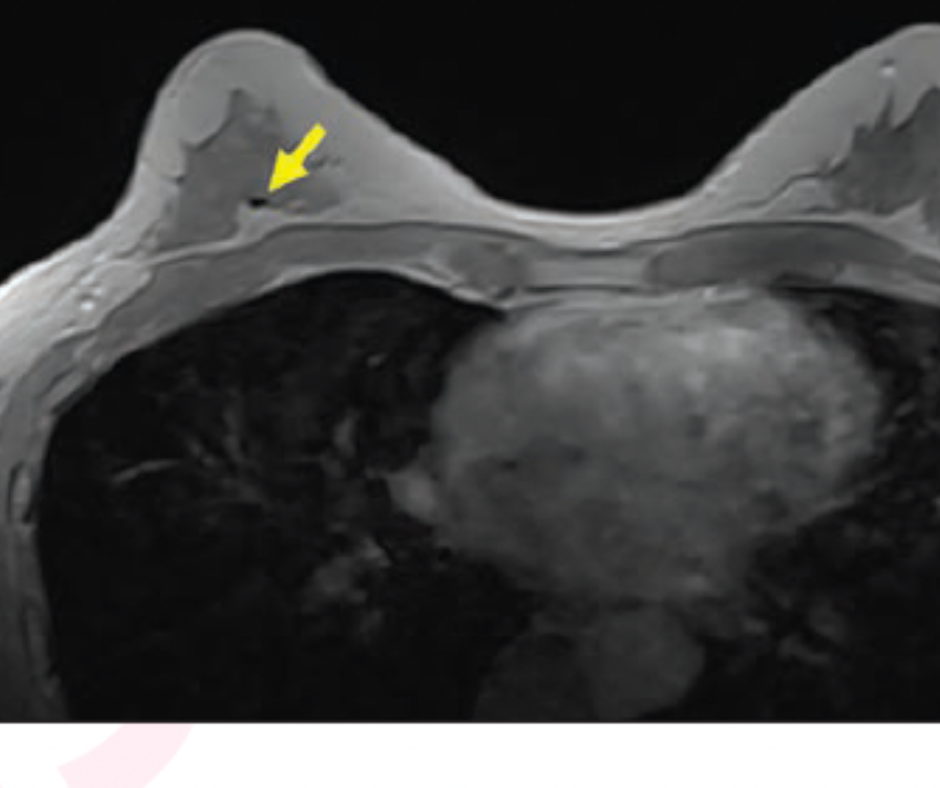

For some patients, identifying biopsy clips on breast magnetic resonance imaging (MRI) may be challenging due to variabilities in the size and shape of the biopsy clips, associated susceptibility artifacts and the types of sequences and acquisition parameters.

Based on the findings of a recently published study looking at four sequences to assess breast MRI for biopsy clips, researchers said the contrast-enhanced, in-phase Dixon sequence provided the highest sensitivity, contrast-to-noise ratio (CNR) and reader confidence in comparison to clinical sequencing techniques.

For the retrospective study, recently published in the American Journal of Roentgenology, researchers reviewed contrast-enhanced breast MRI exams from 164 women with a total of 281 breast biopsy clips. The study authors subsequently compared the contrast-enhanced, in-phase Dixon MRI sequence with three standard sequences including short tau inversion recovery (STIR); T1-weighted, non-fat-suppressed (T1W NFS) sequencing; and first phase sequencing from dynamic, contrast-enhanced T1W fat-suppressed (T1W FS) imaging.

The contrast-enhanced, in-phase Dixon sequence had an 85.1 percent pooled sensitivity rate in comparison to 78.2 percent for T1W NFS, 61.7 percent for T1W FS and 26.6 percent for STIR sequencing, according to the study. The researchers added that the contrast-enhanced, in-phase Dixon sequence also maintained similar positive predictive value (96.4 percent) in comparison to STIR (92.2 percent), T1W NFS (96.1 percent) and T1W FS (92.8 percent).

Baker and colleagues also noted a higher mean contrast-to-noise ratio (CNR) with the contrast-enhanced, in-phase Dixon sequence (4.05) in comparison to T1W NFS (1.21), STIR (0.57) and T1W FS (0.54). They attributed the significantly higher CNR to administration of IV contrast and the absence of fat suppression.

“Fat suppression … is undesirable when identifying biopsy clips because it causes the fat in the breast to become hypointense and therefore closer in signal intensity to the biopsy marker clip,” pointed out Baker and colleagues. “In addition, the administered contrast media reduces anatomic noise by increasing the signal intensity of fibroglandular tissue to approach that of relatively hyperintense fat, thereby reducing the variability of signal intensities present in the underlying breast tissue.”